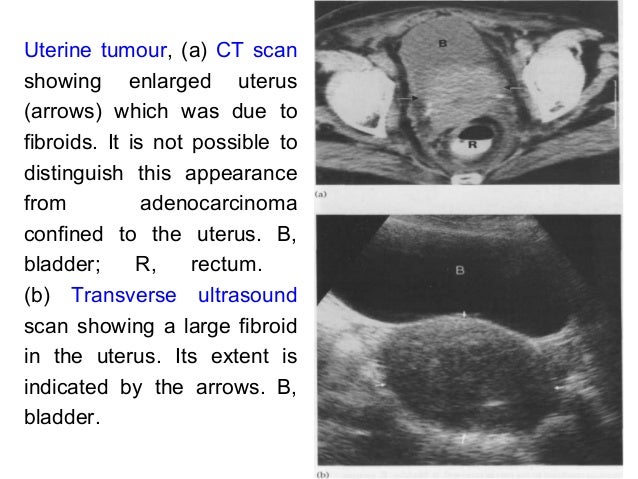

Cancer Of The Female Genital Tract